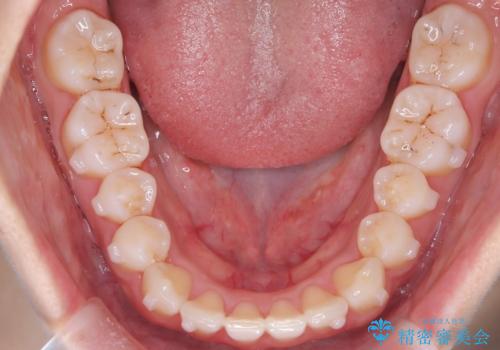

【インビザライン】八重歯が気になる

- 乳歯を抜歯してスペースを確保し八重歯の改善を行いました。

インビザラインをしっかり使用していただいたので、きれいな歯並びになりました。